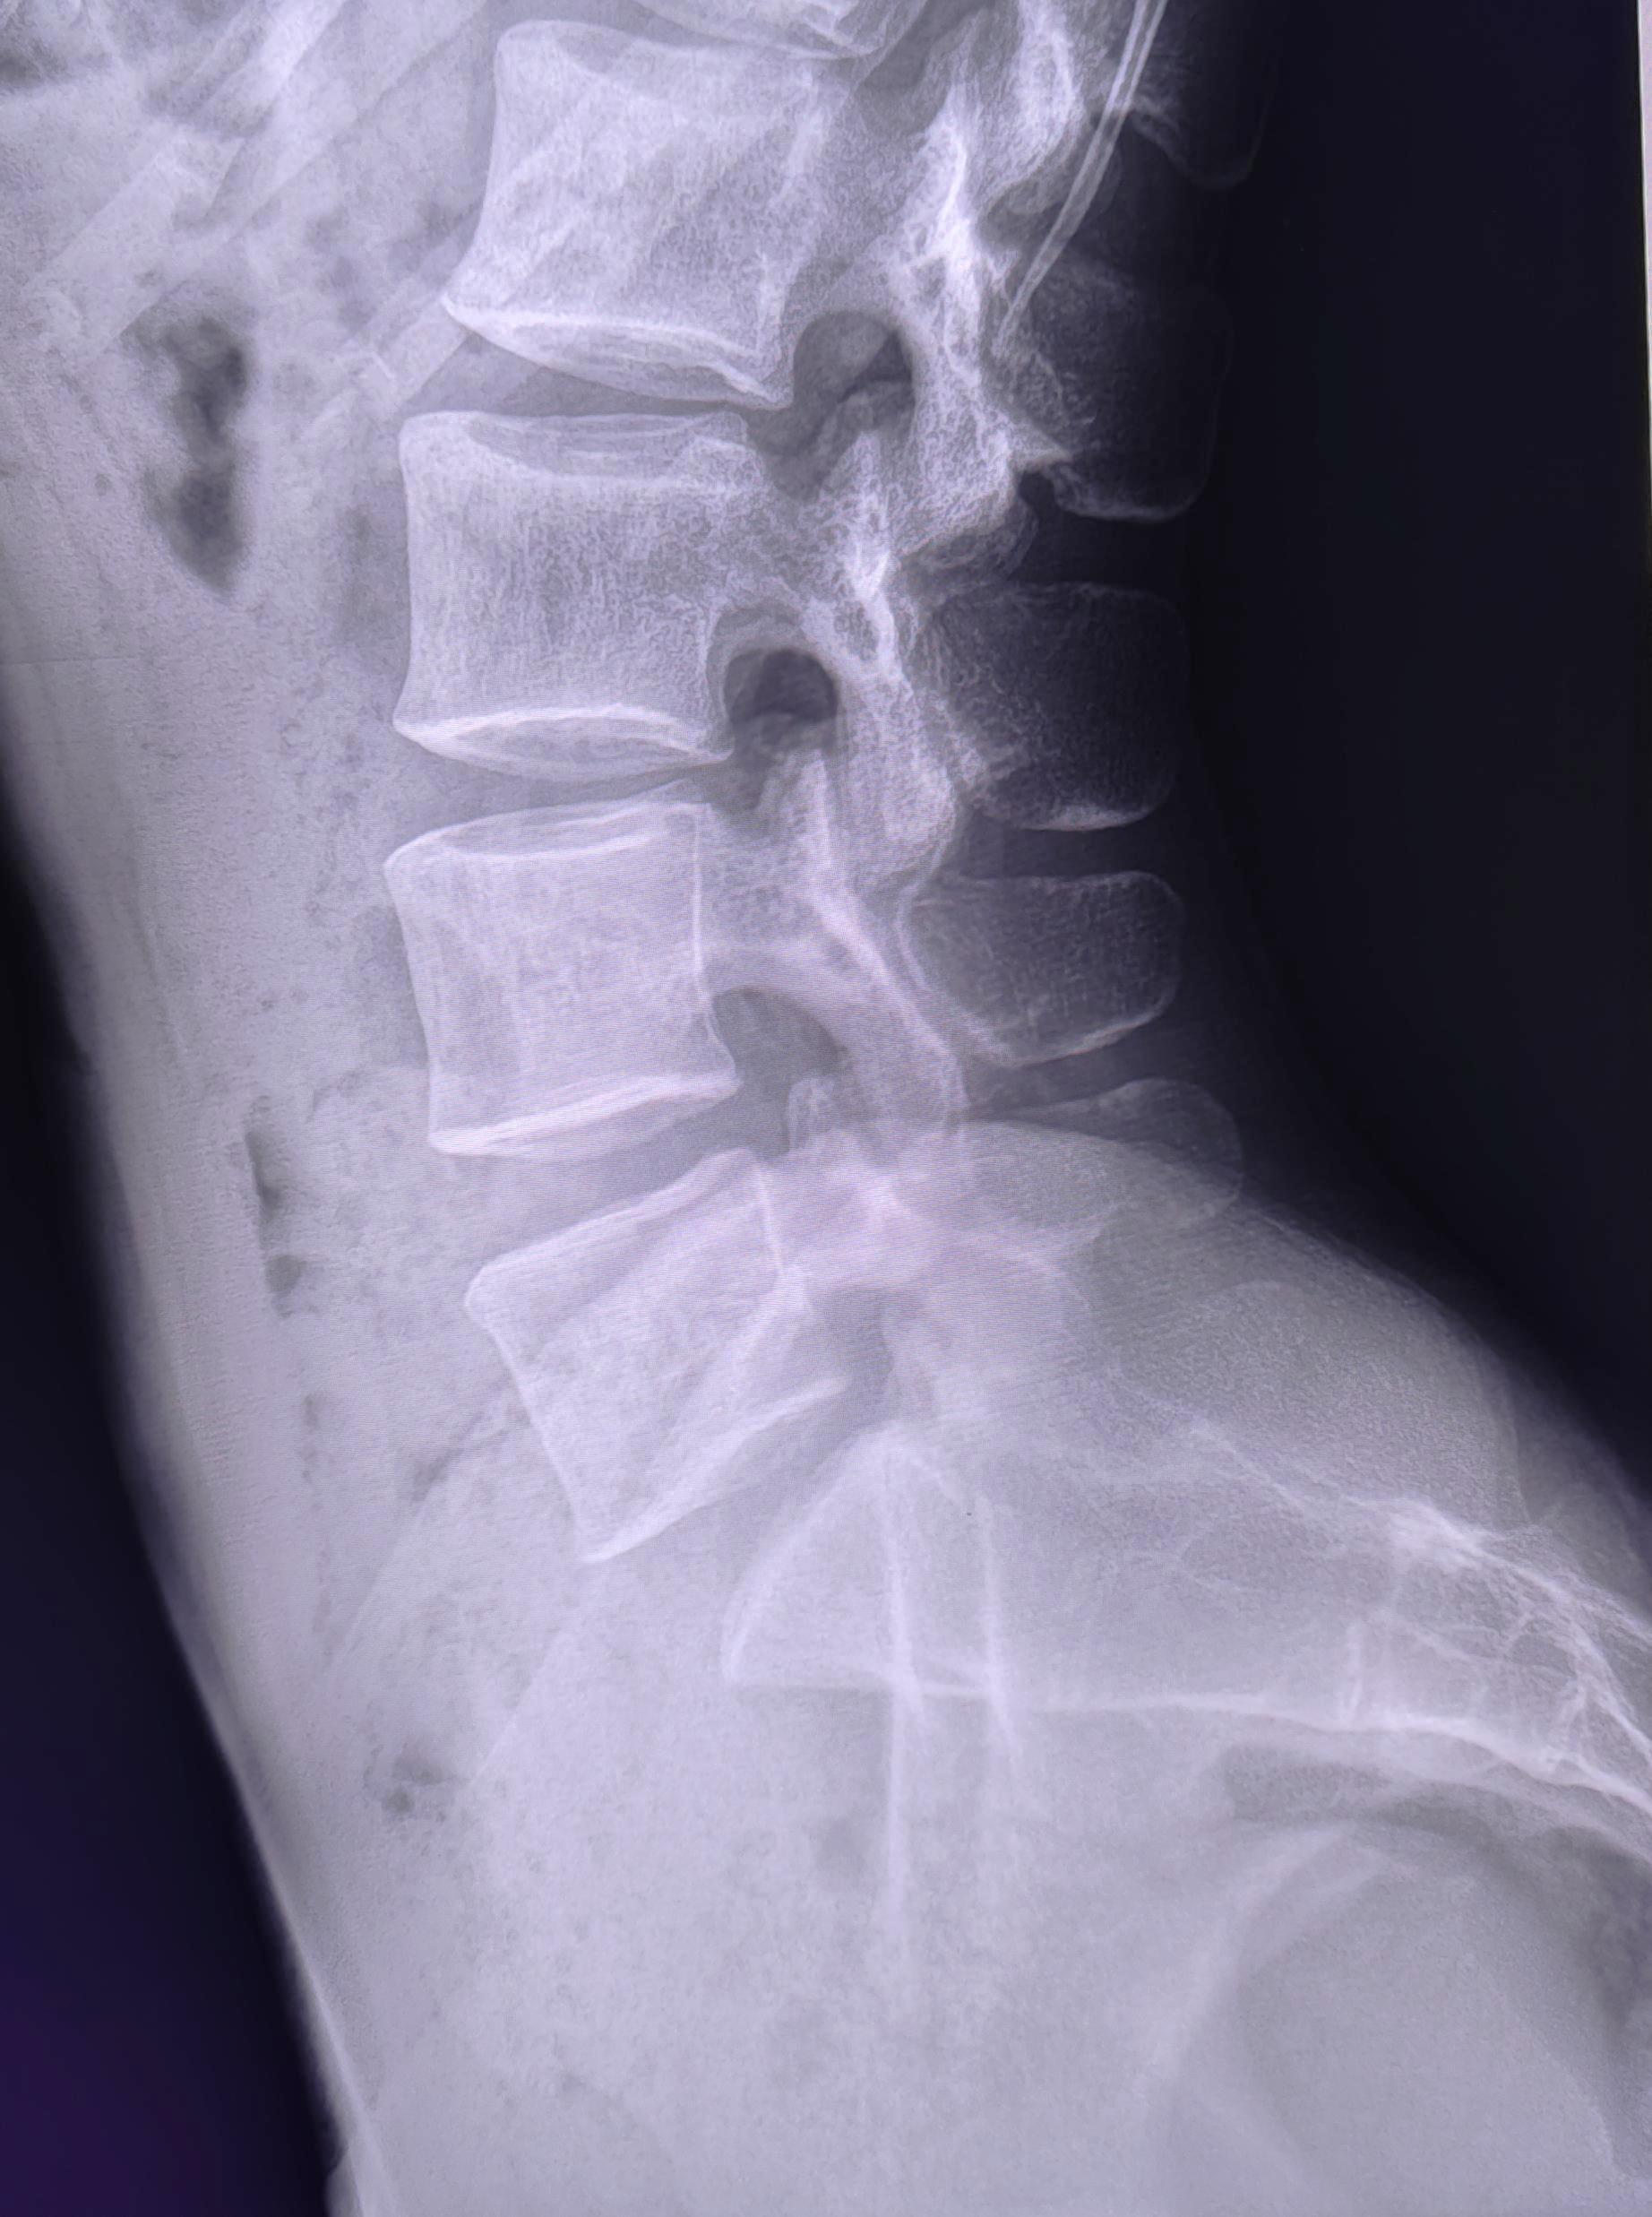

Визуализируется левосторонний дефект дуги L5 позвонка, соотношение задних отделов тел позвонков не нарушено(спондилолистез отсутствует),межпозвонковые щели не сужены, субхондральный склероз замыкательных пластин отсутствует, краевые остеофиты тел позвонков не выявлены. Заключение: Левосторонний спондилолиз L5 позвонка.